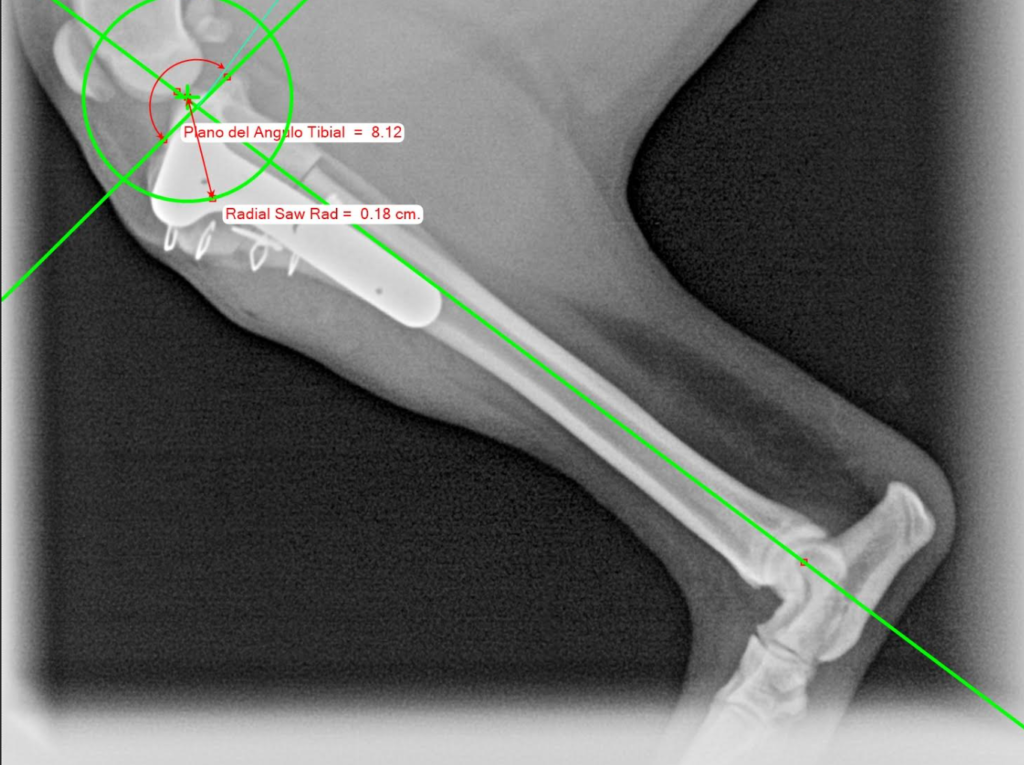

Las lesiones óseas, fracturas y problemas articulares requieren no solo de conocimientos, sino de una precisión quirúrgica milimétrica. Nuestro traumatólogo, Jaime Rey, se encarga de devolver la movilidad y calidad de vida a perros y gatos con lesiones de este tipo.

Tecnología avanzada para diagnósticos y operaciones.